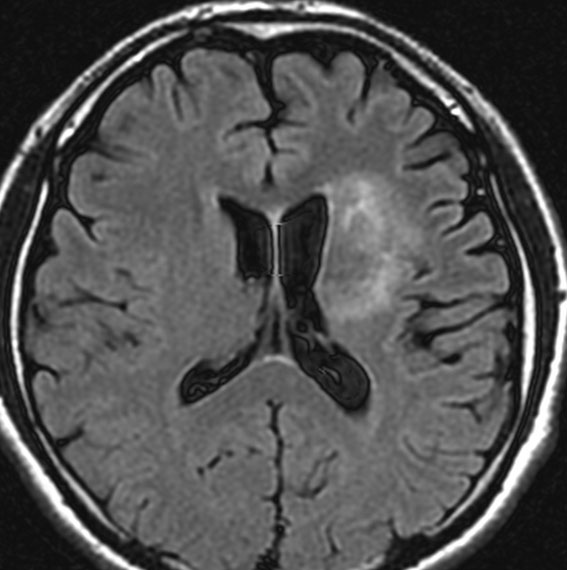

放射線治療前

若い男性です。ある病院で生検術が行われたのですが病理診断がはっきりしませんでした。強度変調放射線治療 IMRT 54グレイ・27分割の放射線治療を行いました。左大脳基底核の乏突起膠腫系腫瘍と考えられたので,増強病変外マージンは10mmととても狭い領域で46グレイ・23分割と低い線量に押さえられています。テモダール 75mg/m2を放射線治療期間中に併用しています。左はガドリニウム増強MRI,右はFLIAR(フレア) 画像。